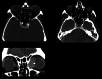

The lacrimal gland is a bilobed serous gland located in the superolateral aspect of the orbit. Lacrimal system pathologies can be broadly divided into pathologies of the lacrimal gland and those of the nasolacrimal drainage apparatus. These include distinct congenital, infectious, inflammatory, and benign, indeterminate, and malignant neoplastic lesions. Trauma and resultant fractures affecting lacrimal drainage apparatus is not part of this review; only non-traumatic diseases will be discussed. CT is the initial modality of choice because of its ability to delineate lacrimal system anatomy and demonstrate most lacrimal drainage system abnormalities and their extent. It also assesses bony architecture and characterizes any osseous changes. MRI is helpful in further characterizing these lesions and better assessing involvement of the surrounding soft tissue structures. In this pictorial review, we will review the anatomy of the lacrimal system, describe CT/MRI findings of the common and uncommon lacrimal system abnormalities and discuss relevance of imaging with regards to patient management.